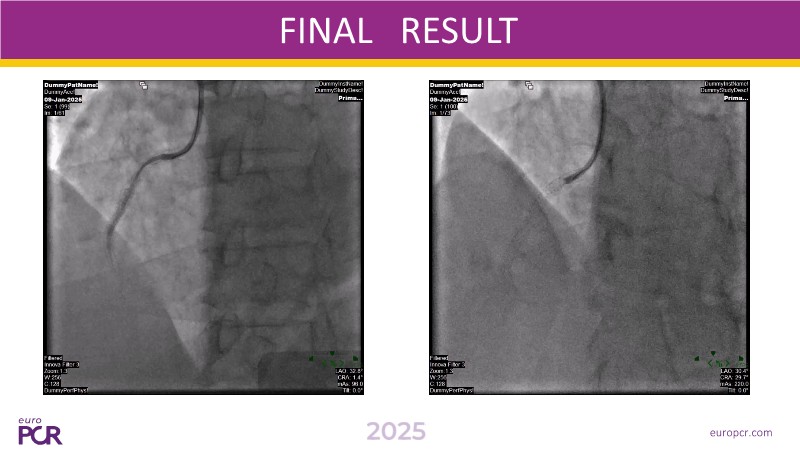

Explore cutting-edge strategies in complex PCI through four detailed clinical cases: a challenging left main bifurcation, a complex procedure using Guideliner Extension Catheters (GEC), an acute coronary syndrome intervention, and treatment of a patient with high bleeding and ischemic risks. This session demonstrates how thorough patient profiling, advanced imaging and functional assessments, and the innovative Cre8 EVO stent technology combine to optimize procedural success and long-term outcomes in complex patients.